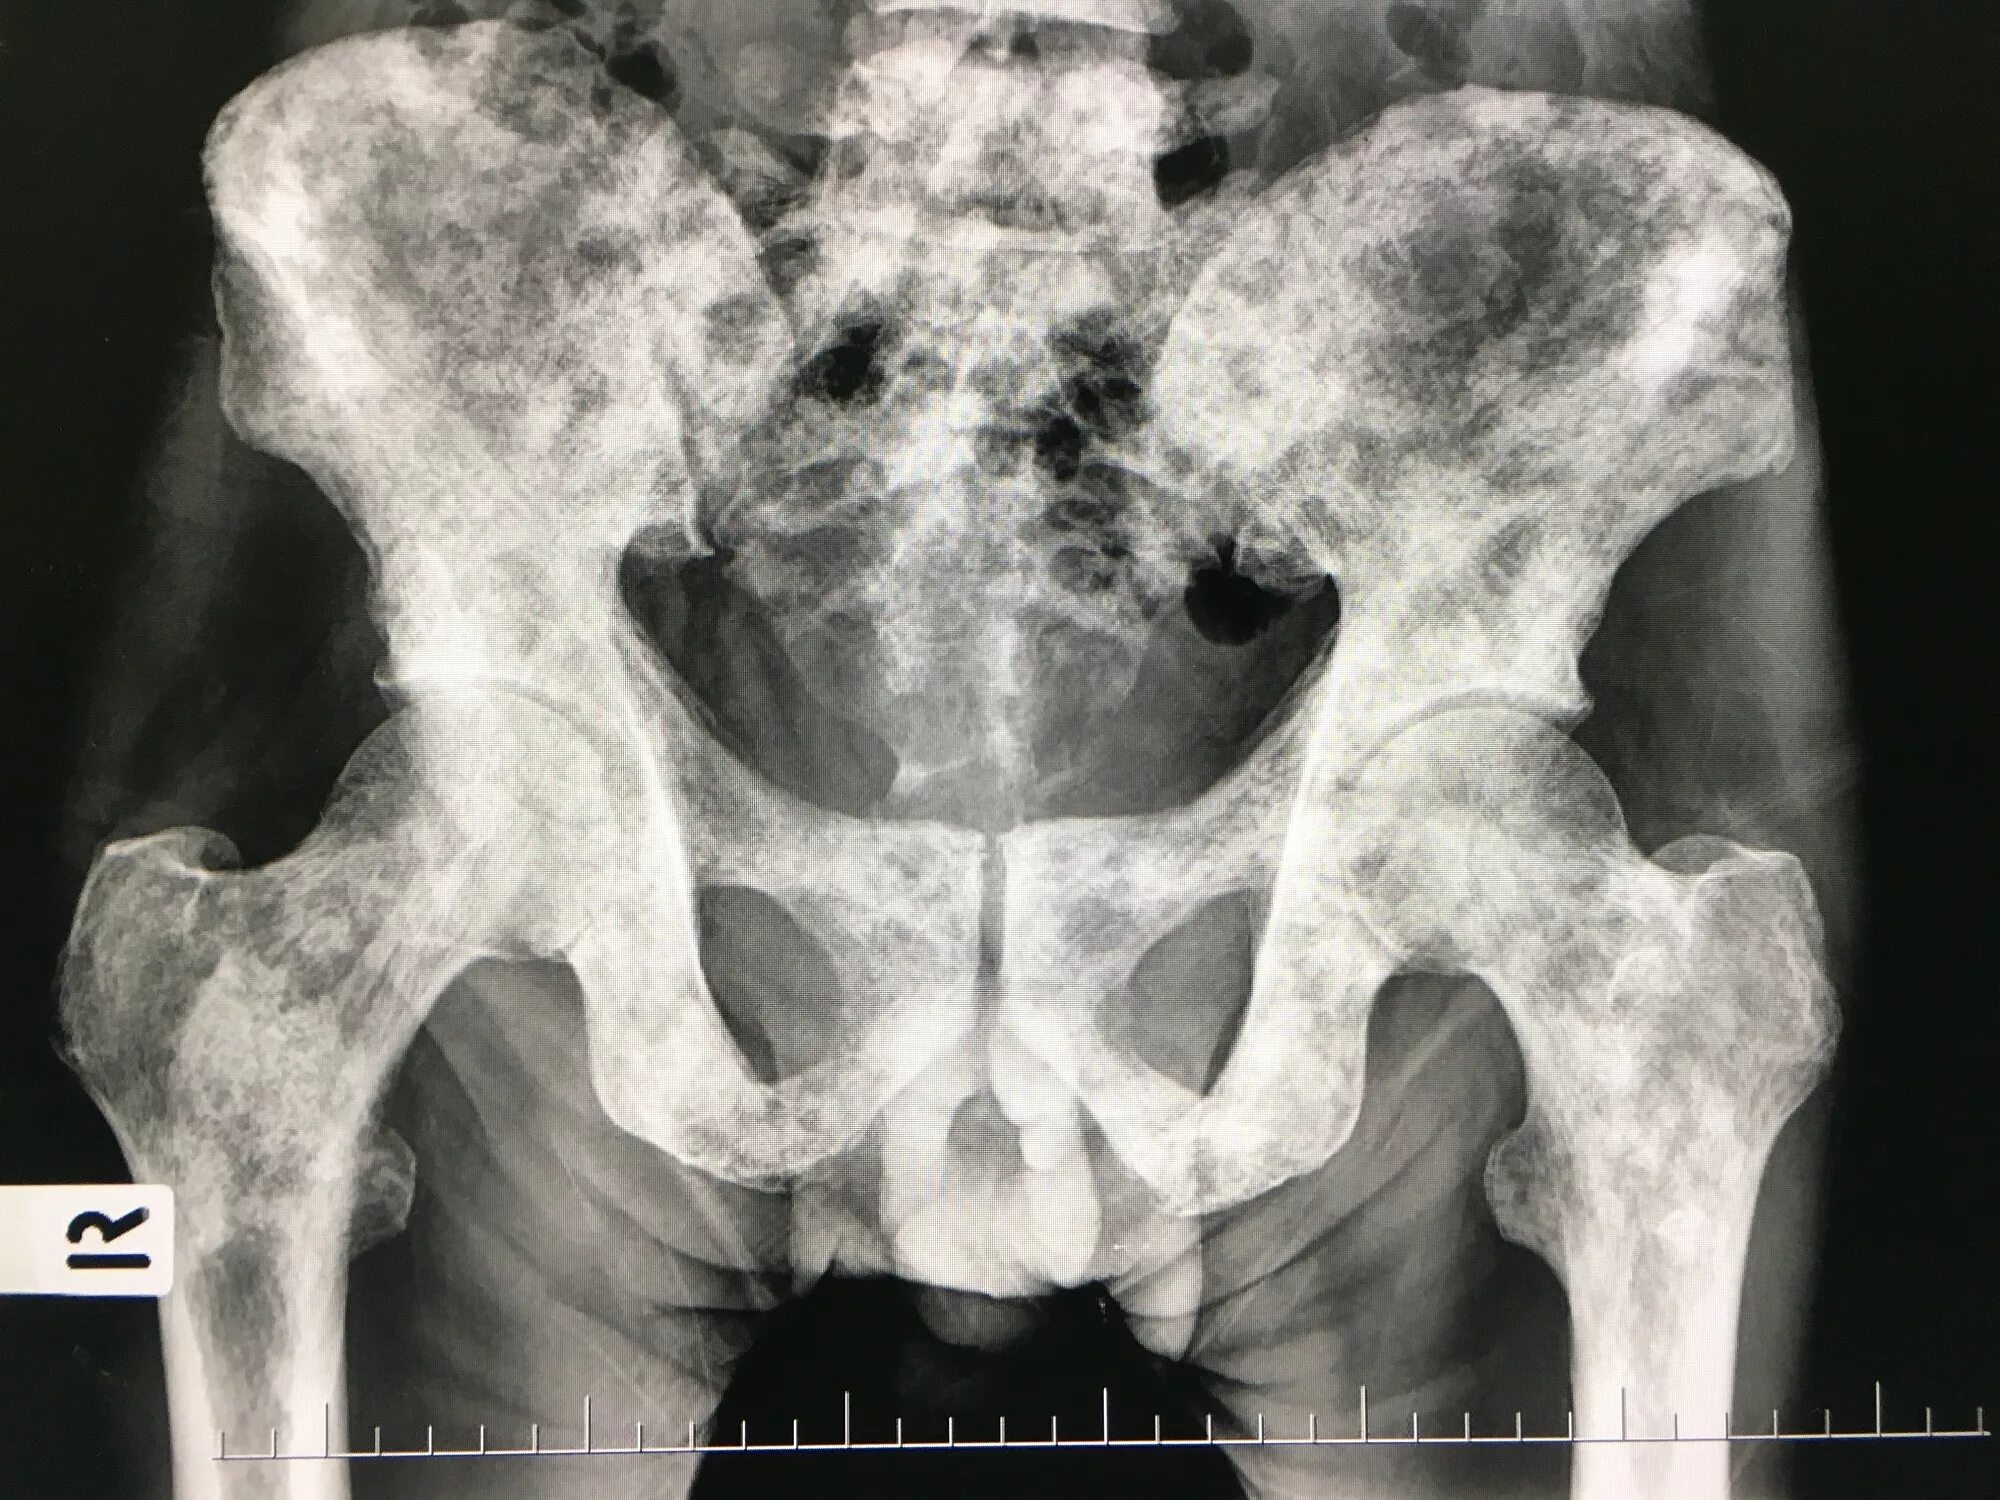

Снимок костей как называется